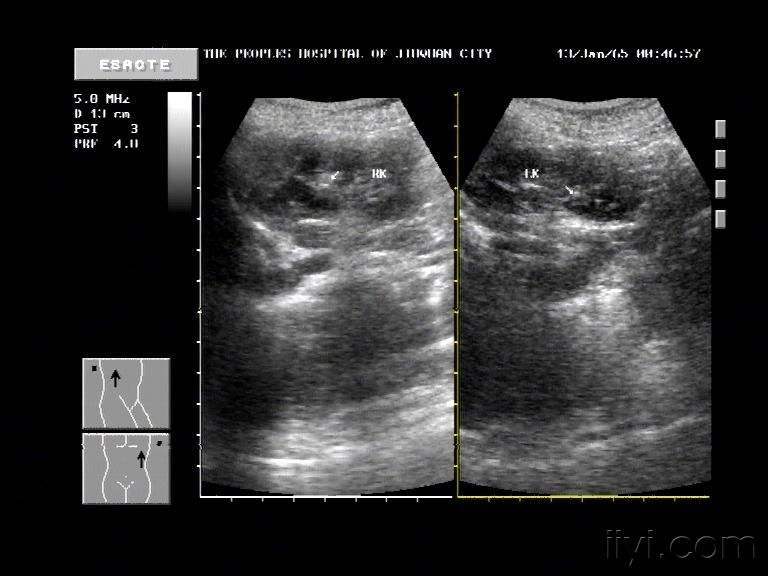

通过彩超、

血、尿常规等检查确诊。